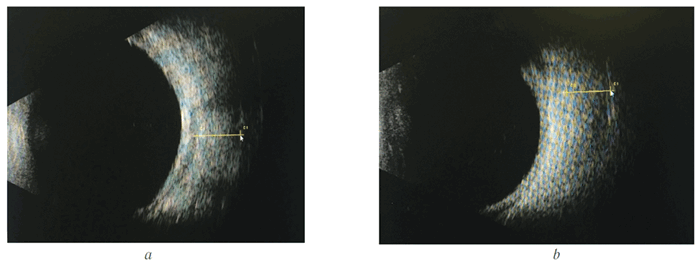

Эхография орбит: нижняя и внутренняя прямая мышцы резко увеличены в размерах (рис. 2).

Рис. 2. Эхограммы орбит того же больного: a — нижняя прямая мышца, 6,5 мм; b — внутренняя прямая мышца, 6,2 мм

Fig. 2. Echograms of patient’s orbits: a — lower rectus, 6.5 mm; b — internal rectus, 6.2 mm

Рис. 6. Эхограммы орбиты (по окончании лечения): a — нижняя прямая мышца, 5,6 мм; b — внутренняя прямая мышца, 5,46 мм

Fig. 6. Echograms of orbits after treatment: a — lower rectus, 5.6 mm; b — internal rectus, 5.46 mm